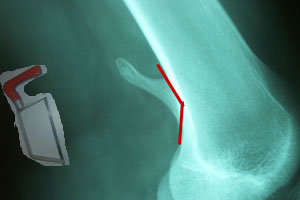

Excision!